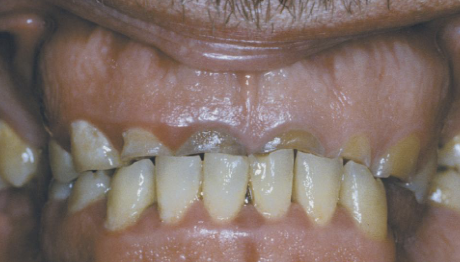

AD, AR, X-linked; both deciduous and permanent dentition are diffusely involved, affects enamel (soft, thin, easily damaged, susceptible to decay), dentin is exposed

amelogenesis imperfecta (AI)

Clinical appearance of AI

yellow-brown to white pitted lesions, open bite, loss of contact